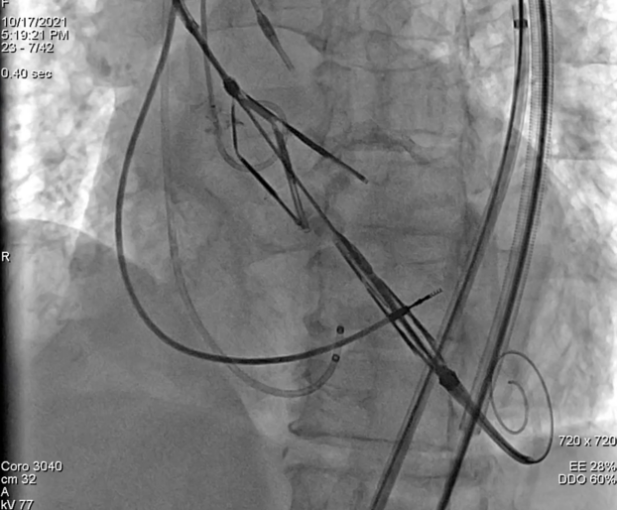

2021年10月17日,华中科技大学同济医学院附属协和医院董念国教授团队,与中国医学科学院阜外医院吴永健教授南昌大学第一附属医院彭小平教授姜宇教授共同协作下,顺利完成创新器械Leaflex™ Performer经导管主动脉瓣膜修复系统联合TriGUARD3™抗栓塞远端脑保护装置全球首例人体应用。

Leaflex™ Performer 联合TriGUARD3™全球首例临床应用成功

TriGUARD3™脑保护装置精准定位,完全释放